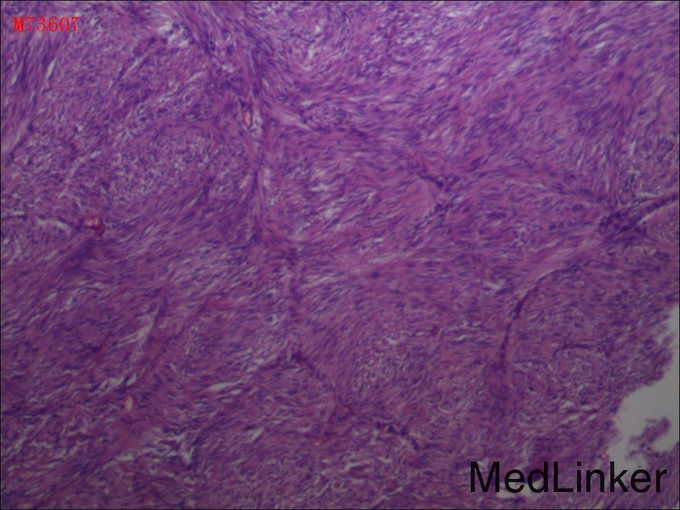

诊断:1.急性上消化道出血,2.胰头占位性病变3.十二指肠降部溃疡 治疗:完善术前检查,在全麻下行“根治性胰十二指肠切除术”,术程顺利,术后病理提示:十二指肠间质瘤,高危险度;出院后休息两周予格列卫口服化疗。

患者慢性贫血与消化道长期失血有关,当地仅凭一次胃镜活检未提示恶性病变,便只以良性病变诊治,应该说不全面。对于向腹腔外生性生长的肿瘤,内镜很多时候取不到合适的标本,此时需借助增强CT等影像学评估肿瘤生长情况。